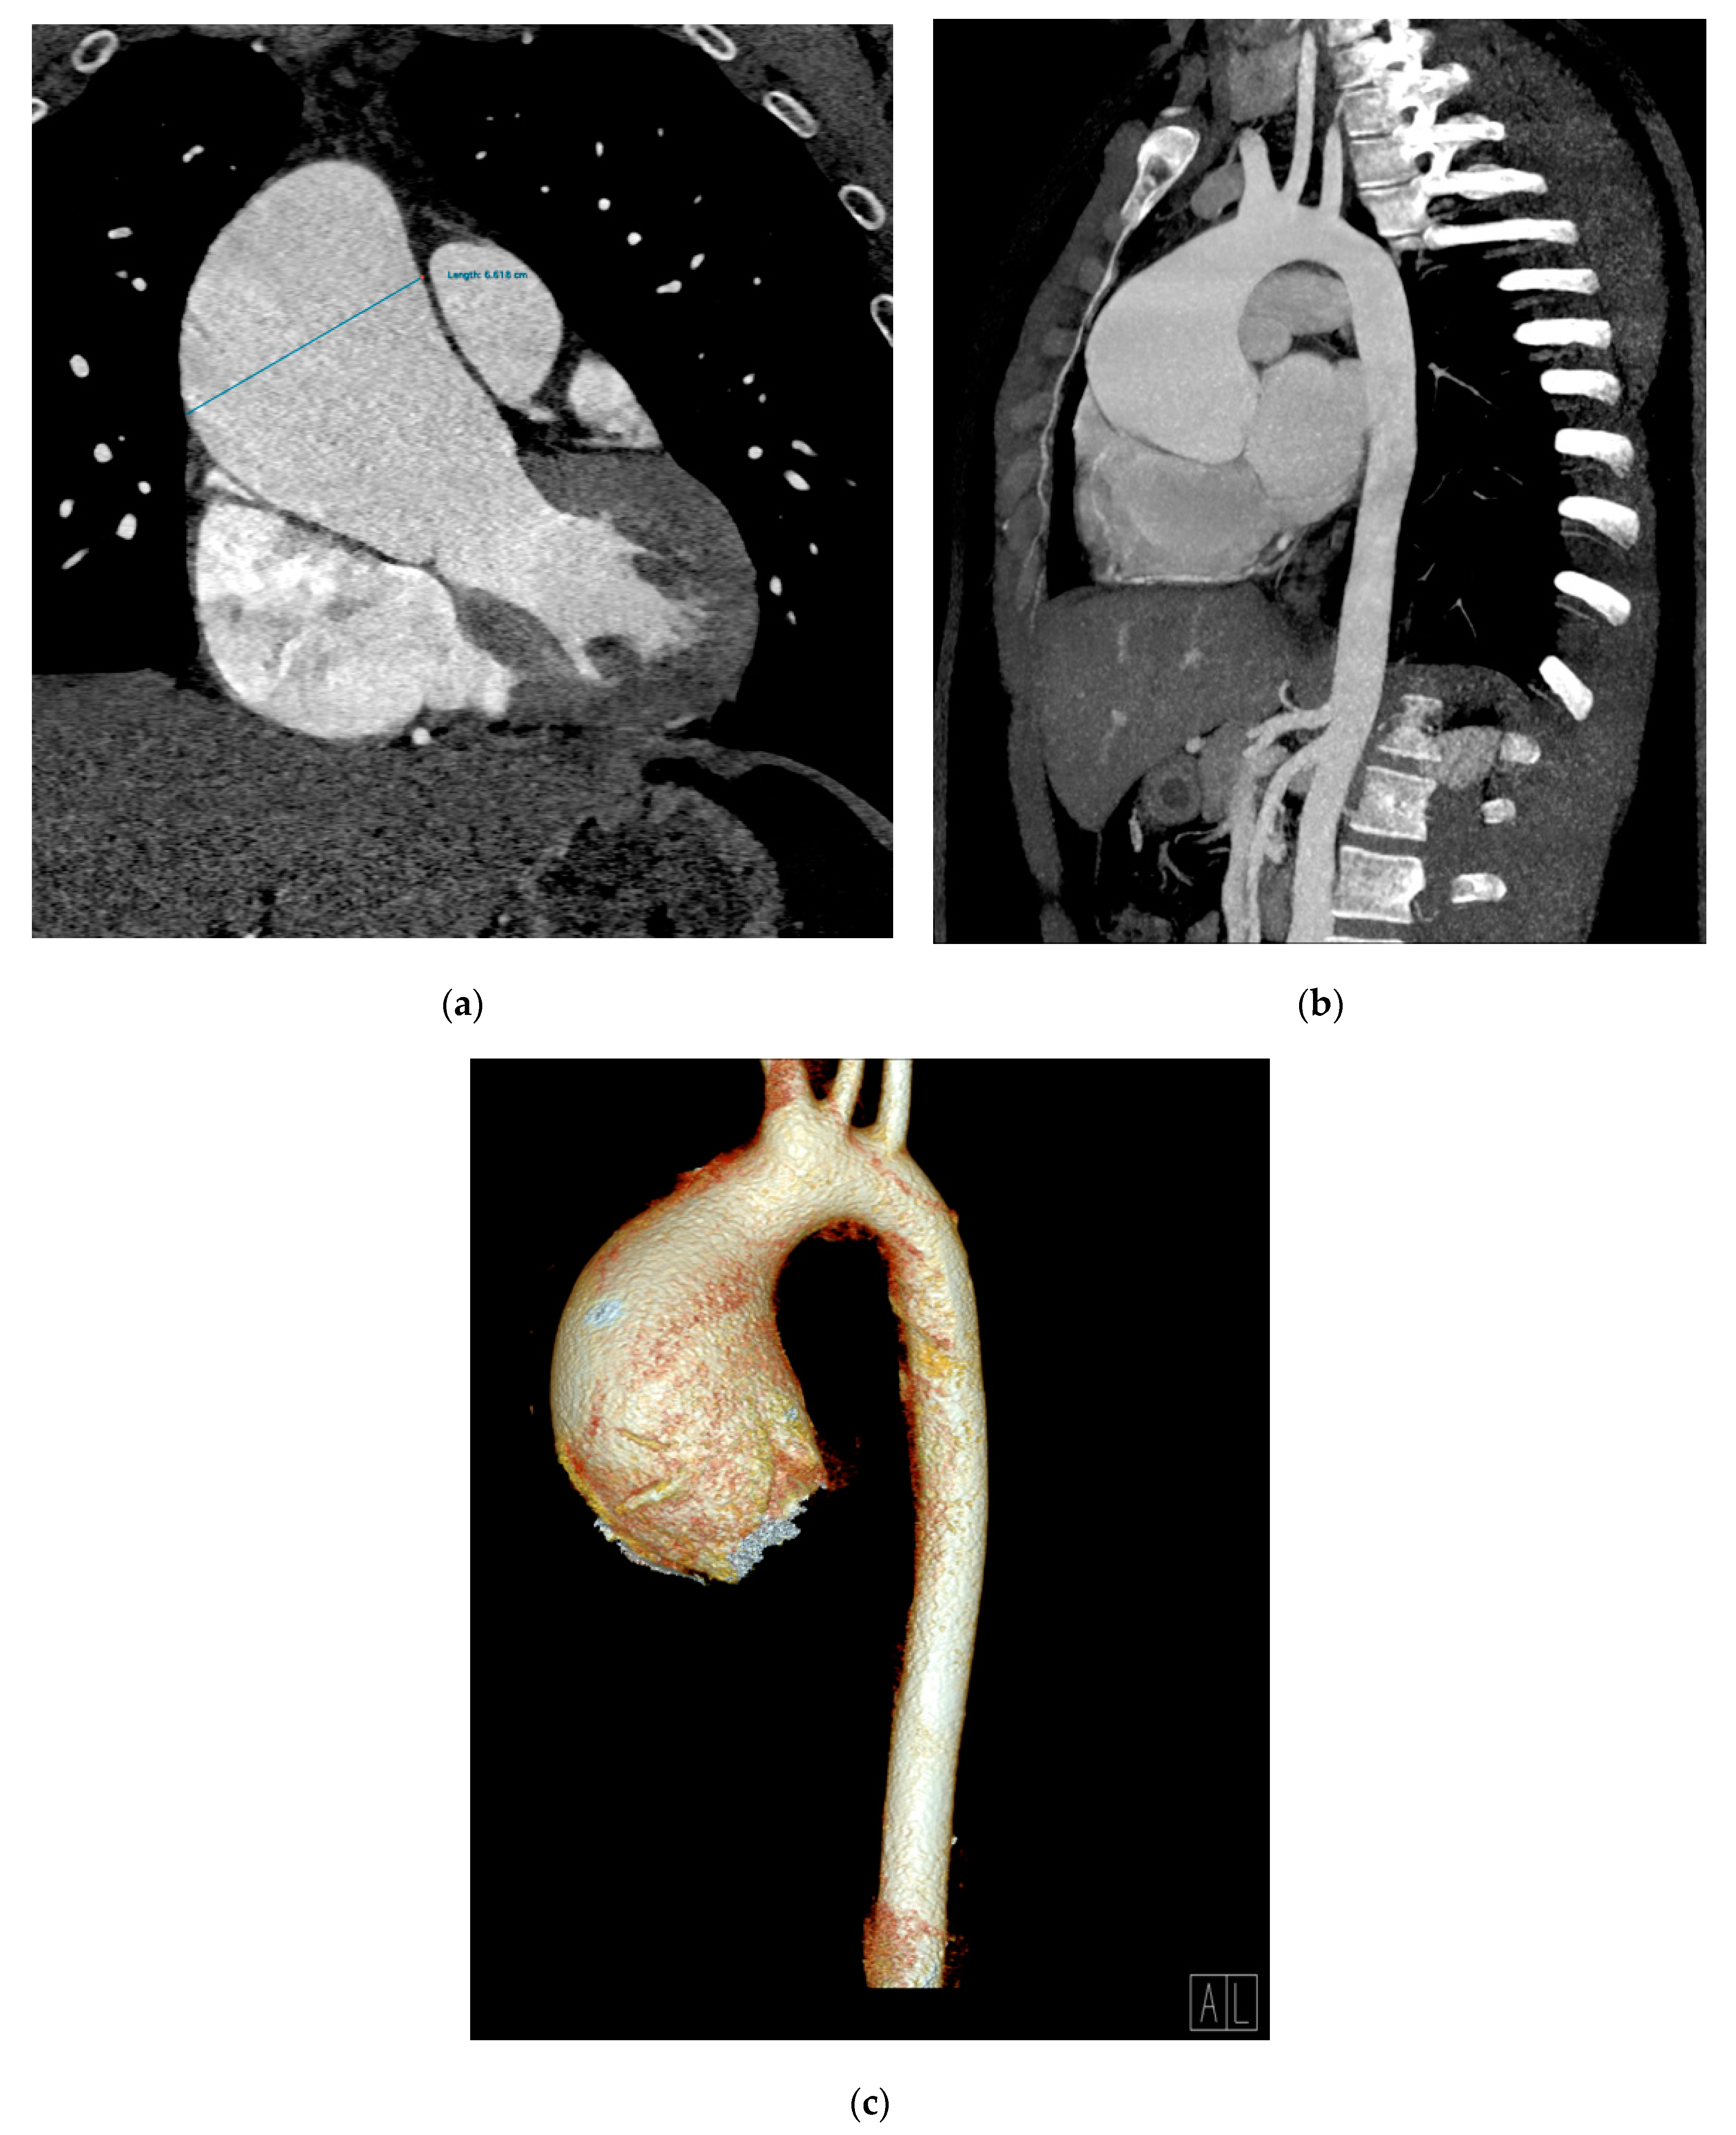

2. Case Presentation